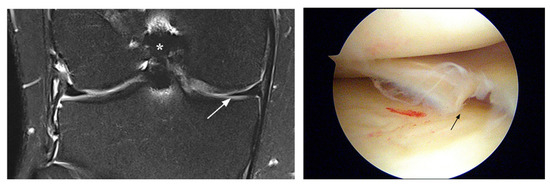

3.2. Interpretation Errors

| 16 | M, 45 y | 80 | missed peripheral tear posterior horn | unstable tear posterior horn | chronic | R |

| 17 | M, 40 y | 10 | missed posterior root tear | oblique root tear | acute | R |

| FN LM | ||||||

| 18 | M, 48 y | 50 | missed posterior root tear | posterior root tear | acute | R |